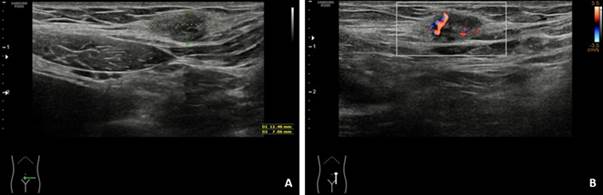

Se realizó ecografía y tomografía computarizada (TC) en Valsalva, donde se apreció pequeño saco herniario supraumbilical de 1,1 cm, sin más defectos fasciales ni sacos. En el tejido celular subcutáneo de la región inguinal izquierda, se observó un nódulo hiperdenso de 2 cm que se definió como foco de endometriosis en pared. Los ovarios eran globulosos por endometriomas (Figura 1).

Figura 1: Ecografía en modo B y ecografía power-doppler. A) En el tejido celular subcutáneo de la pared abdominal, ligeramente por encima del ligamento inguinal izquierdo y adyacente a la cicatriz de cesárea previa, se visualiza un nódulo de ecogenicidad heterogénea, predominantemente hipoecoico, de contorno irregular. B) Presenta aumento de vascularización en doppler, con vasos con flujo de alta resistencia en doppler pulsado.